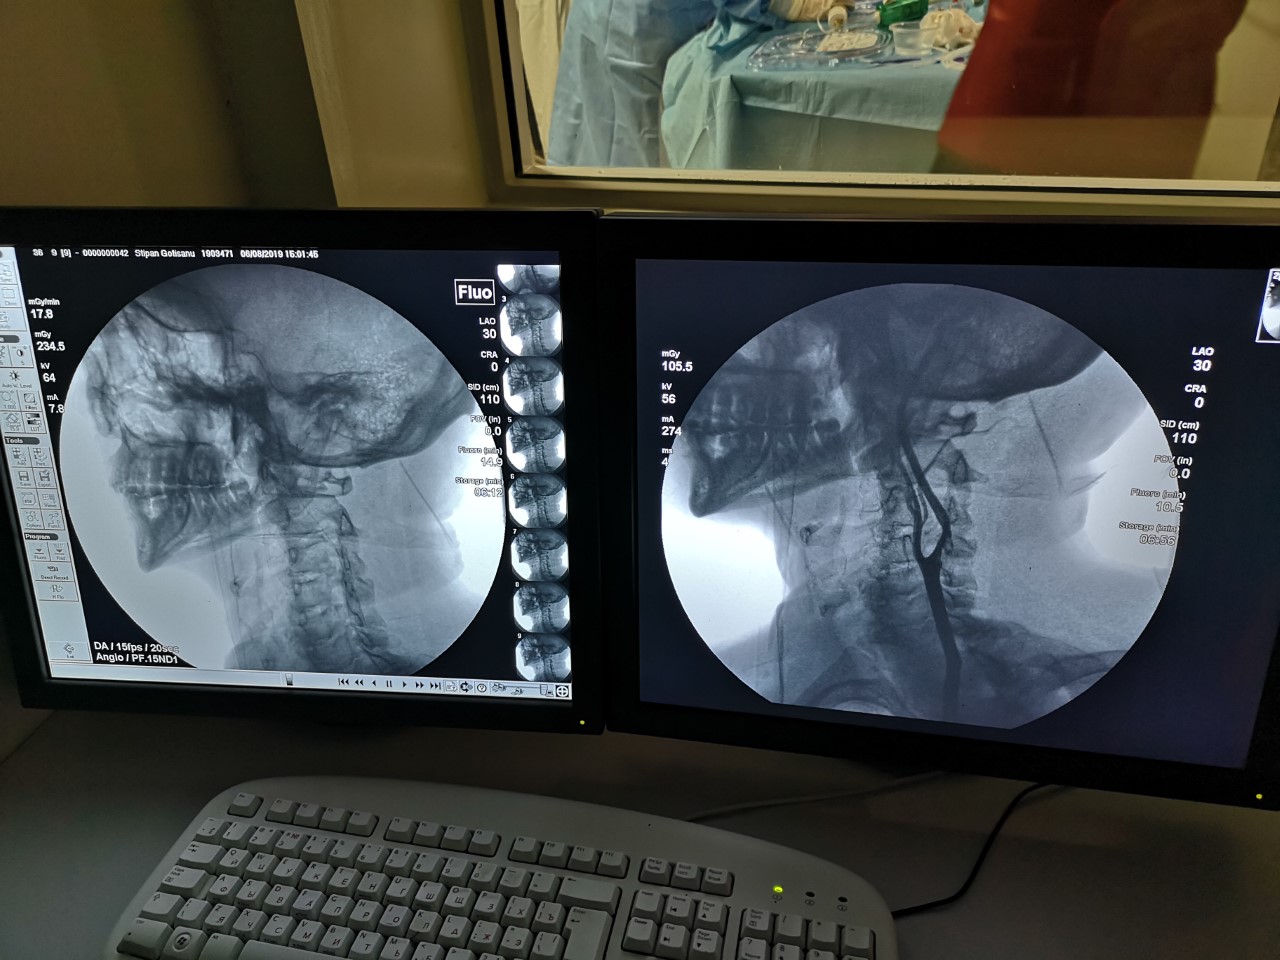

În jurul orelor 16.00, marți, primul care a fost operat a fost pacientul S. G. Echipa formată din medicul neurochirurg Ion Preguza, asistenta medicală și alți doi medici au fost ghidați de profesorul Ion Popovici, invitat special la o primă intervenție de acest gen.

Și-au îmbrăcat pe rând halatele de operație, au pregătit instrumentarul,

iar de cealaltă parte a geamului fumuriu au fost monitorizați de viitoarea

echipă de medici specialiști, care urmează să fie pregătiți pentru astfel de

intervenții.

De aici nu se auzeau discuțiile dintre medici, dar se simțea atmosfera de încordare, neliniște, dar și de satisfacție a medicilor, care de acum încolo vor salva vieți, aici, acasă.

„Emoțiile după operație au fost de învingător. Intervențiile au decurs conform planului preoperator, fără evenimente neprevăzute. Echipa a dovedit că și în condițiile Republicii Moldova, pacienții pot primi asistență specializată de nivel european”, a precizat Ion Preguza, după cele două intervenții și o noapte în care a fost de gardă.